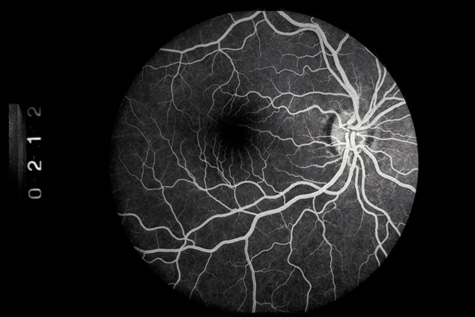

Commotio retinae (Latin, meaning retinal contusion) is a contrecoup injury. It can occur peripherally (Fig. 8) or centrally, in which case it is called Berlin's edema (Fig. 9). Immediately and for several hours after the trauma, the retina appears normal, although the patient may complain of decreased vision. Thereafter, the outer layers of affected retina become opaque. On fluorescein angiography, the opaque retina blocks background choroidal fluorescence, and in most cases there is no leakage into or under the retina (Fig. 10). For years, clinicians had difficulty explaining this blockage, because leakage is expected in conditions with edema. It was then shown in experimental animals and in human autopsy eyes that Berlin's edema is not true edema. The retinal opaqueness is the result of intracellular edema and fragmentation of the photoreceptor outer segments and intracellular edema of the underlying pigment epithelium. There is little or no intercellular fluid.66–69

Fig. 8. Peripheral commotio retinae. The retinal blood vessels are clearly seen because the retinal whitening is in the outer retinal layers.

Fig. 10. A: Commotio retinae in the macula. B: On the angiogram there is no leakage in the area of commotio retinae.